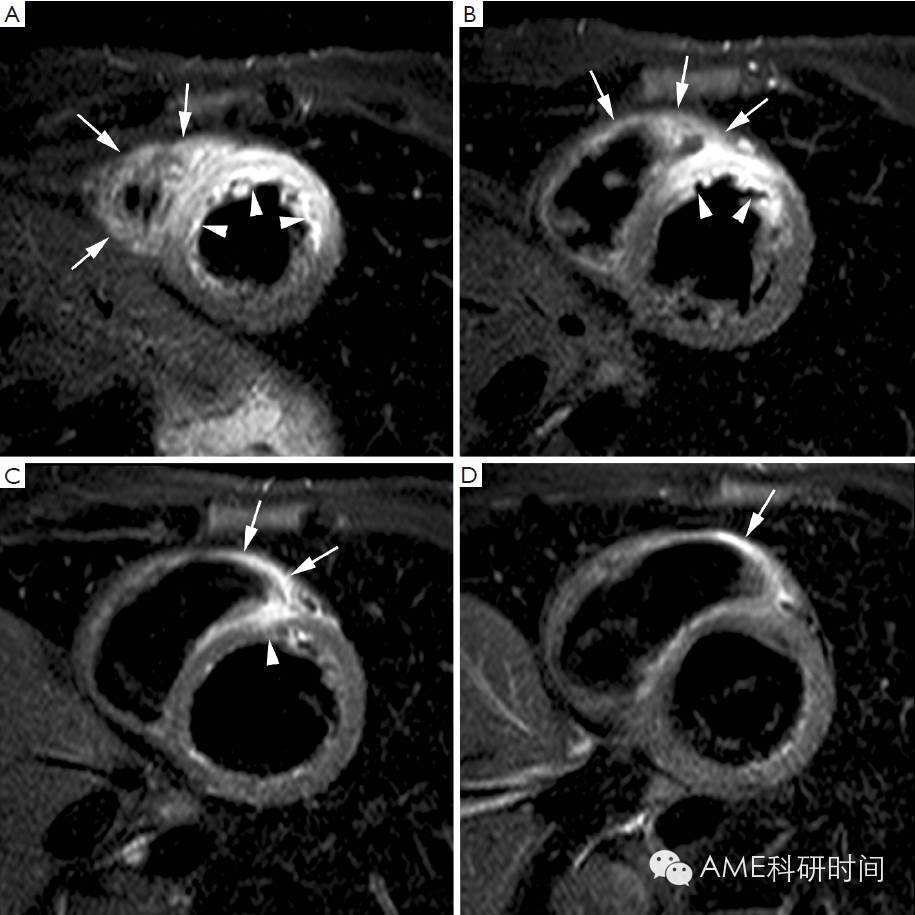

由于LGE-MRI的高空间分辨率以及在正常和坏死心肌间信号强度的差异增加,因此对心肌梗死的成像具有极高的准确度和良好的重现性,优于其他成像方式,如SPECT(26,27)。因此,LGE-MRI使得可以对不可逆损伤心肌进行精确和可重复现的量化,即通过评价坏死心肌的透壁性(心内膜下还是透壁)和质量(坏死或纤维化的量)。梗死透壁可采用半定量评分表示,例如将心肌壁分成等距的4段(26),或使用自动定量的方法(28)。此外,还可以很容易地检测到虽结构小但功能重要的心脏结构(如肌或右心室壁)梗死。目前用于检测右心室梗死的技术低估了其真实发生率(29)。在最近的研究中,我们观察到在急性左心室下端梗死的患者中,右心室水肿和LGE发生的比率分别为75%和54%(30)(图4),而急性左心室前端梗死的患者中,右心室水肿和LGE发生的比率分别为33%和11%,这是因为前外侧的右心室壁有相当部分是靠冠状动脉前降支的细小分支灌注的。在心肌梗死后4个月,持续性的右心室壁LGE,与局部或整体右心室的功能未恢复有关。LGE-MRI可显示小至1 g的心肌坏死,使其成为描绘经皮冠状动脉介入治疗后梗死的理想技术。经皮冠状动脉介入治疗后心肌梗死,在LGE-MRI中显示两种信号形式,即与支架附近侧支闭塞有关的“相邻”的心肌坏死,和斑块材料远端栓塞引起的“远端”心肌坏死(31)。

图4 Nearly isolated RV infarction in 82-year-old woman. Short-axis cine at end diastole (A) and end systole (B), short-axis T2 weighted STIR imaging (C). Late gadolinium imaging in short-axis (D), horizontal long-axis (E) and RV vertical long-axis (F). Moderately dilated and dysfunctional RV (EDV: 197 mL, EF: 39%) and nearly normal LV volumes and function (EDV: 109 mL, EF: 63%). Diffuse RV myocardial edema (arrowheads, C) with limited edema in inferoseptal LV wall (arrow, C). Late gadolinium imaging shows diffuse RV myocardial enhancement (arrowheads, D,E,F). Focal transmural enhancement in inferoseptal LV wall (arrow, D). Note the presence of some pericardial enhancement along the lateral LV border (arrows, E). Adapted from Ischemic Heart Disease by Bogaert J and Dymarkowski S, in Clinical Cardiac MRI Second Edition, Bogaert J, Dymarkowski S, Taylor AM, Muthurangu V (eds). Springer Heidelberg, Germany (ISBN 978-3-642-23034-9).